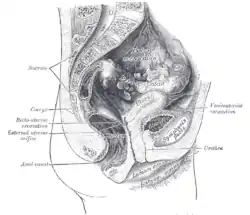

Median sagittal section of male pelvis Median sagittal section of female pelvis

Median sagittal section of female pelvis